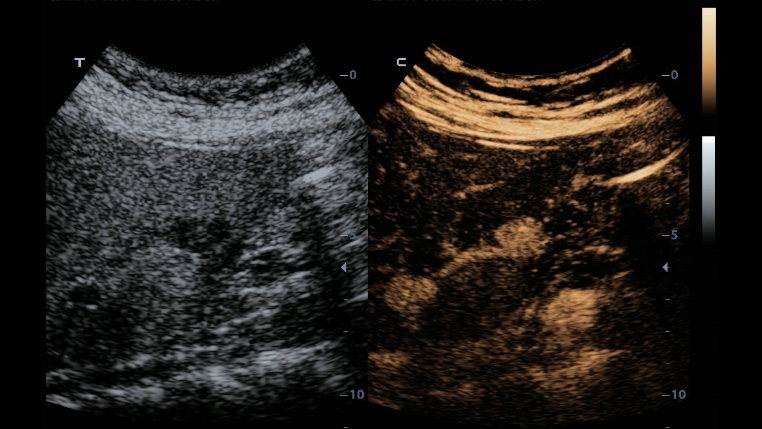

Teknologi pencitraan klasik: meningkatkan mutu diagnosis

Dengan penerapan teknologi pencitraan klasik, yang dimigrasikan dari sistem ultrasound yang sudah terbukti, DC-40 dengan Full HD memberikan peningkatan mutu akan detail gambar.

- iClear (teknologi pencitraan reduksi speckle)

- PSH (Pencitraan Phase Shift Harmonic)

- iBeam: Teknologi spatial-compounding imaging

Seri produk transduser yang dioptimalkan: cakupan aplikasi yang luas

Dengan kombinasi transduser serbaguna, DC-40 dengan Full HD menghadirkan keseimbangan kinerja terbaik dalam berbagai jenis aplikasi, dan menghasilkan mutu gambar yang lebih baik untuk berbagai macam jenis pasien.